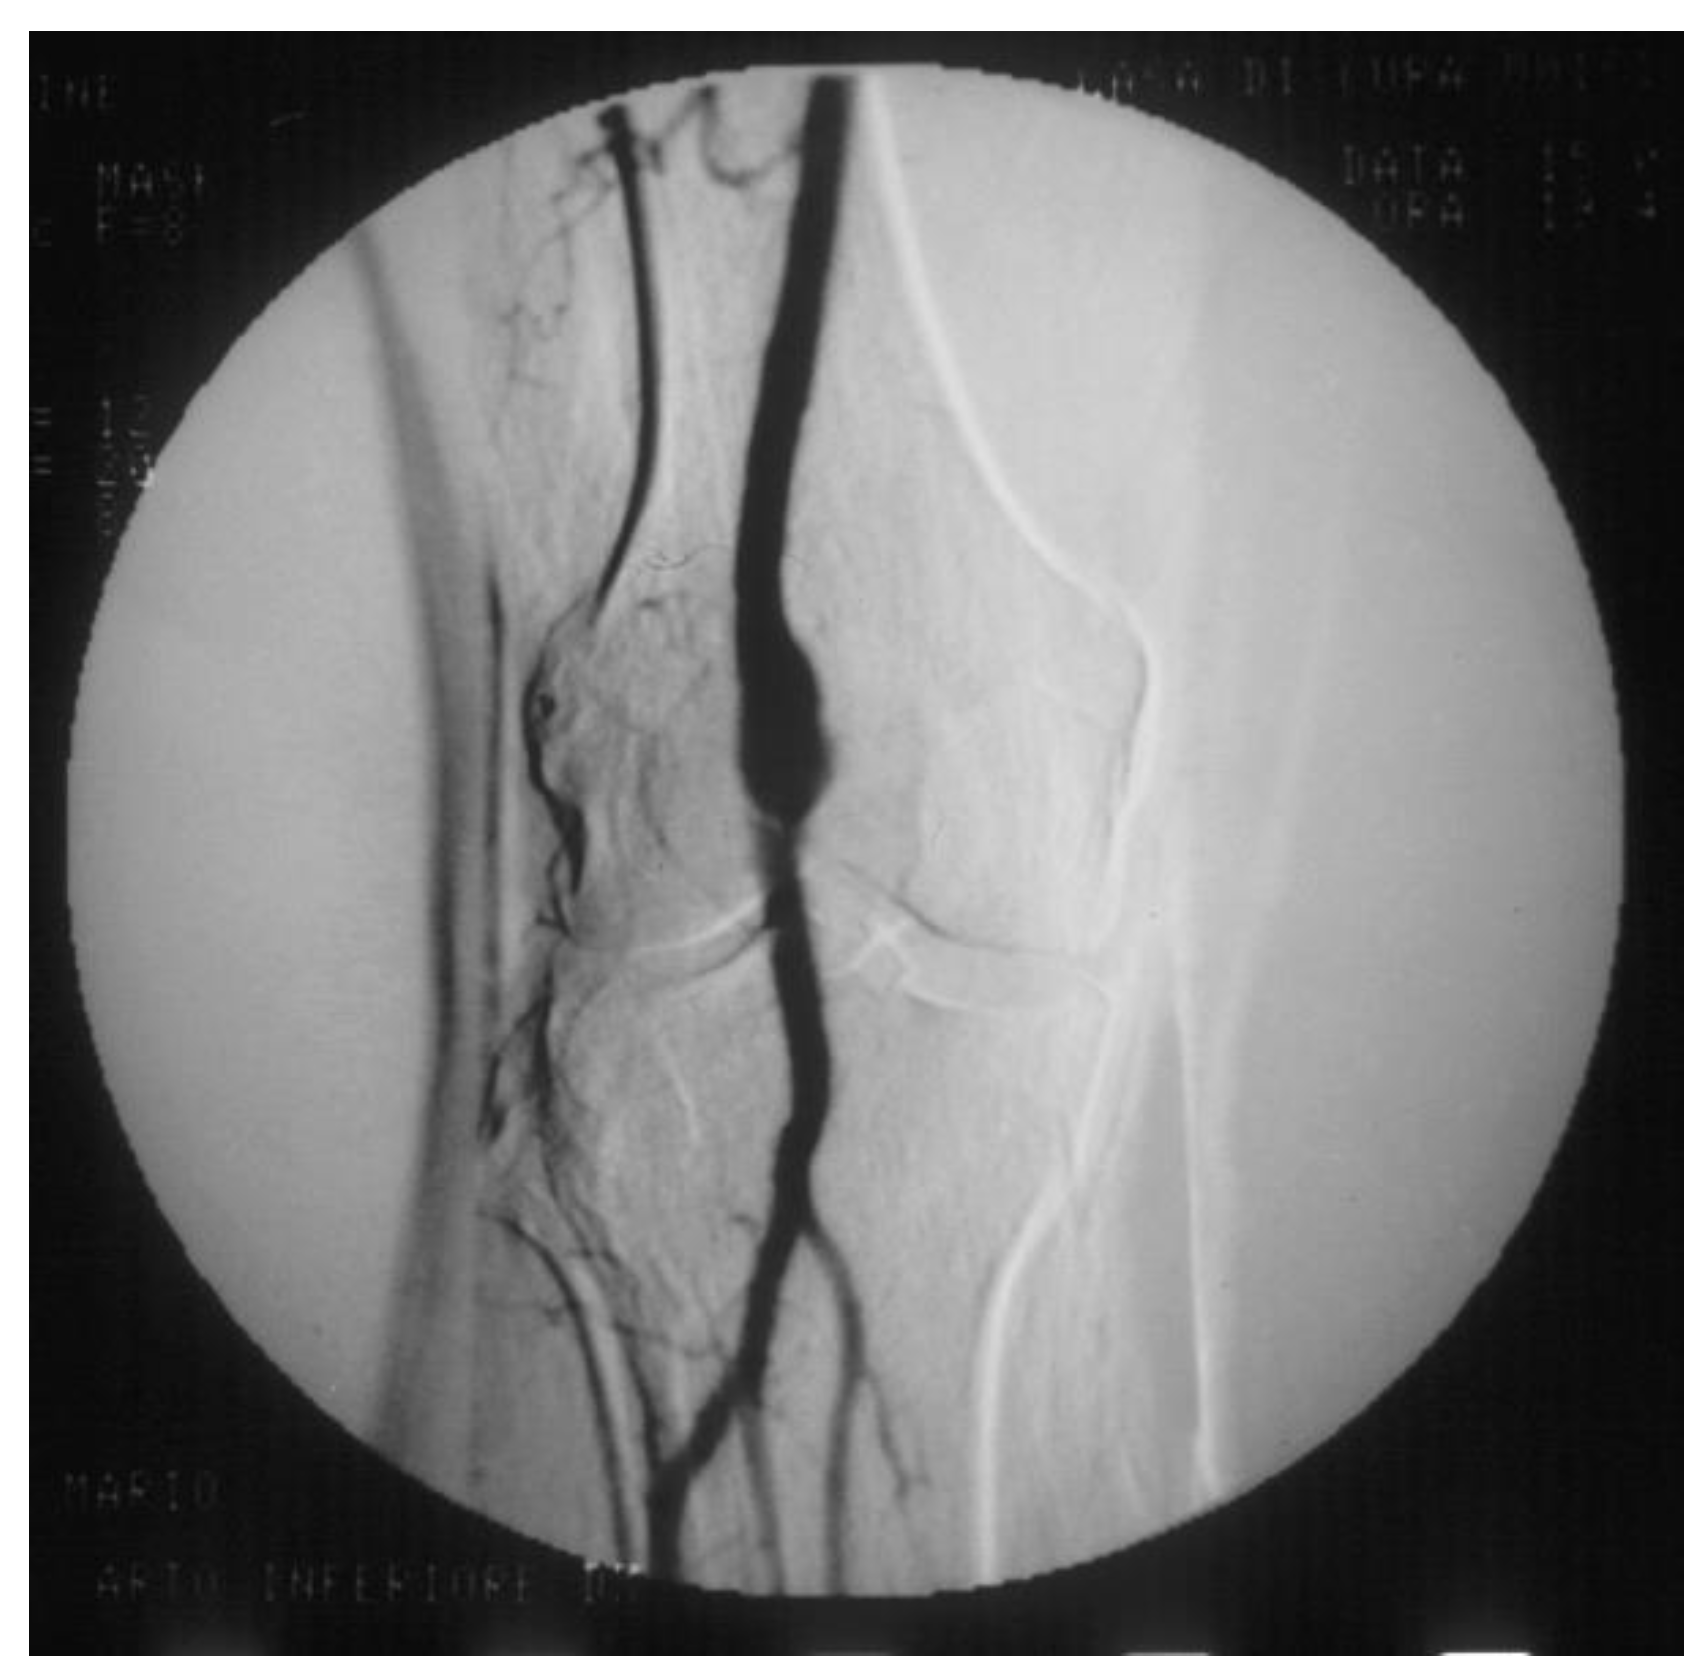

PAAs should be detected not so much for the risk of rupture, which is rare, but for their risk of embolization and thrombosis. The physiologic flexion of the knee can act as a tremendous stress for the parietal thrombus of the PAA, potentially causing paroxysmal, multiple, and insidious episodes of asymptomatic microembolization to the tibial arteries (Figure 11). As a consequence, the latter can progressively obstruct, drastically reducing the run-off of the popliteal artery and giving rise to a clinical picture ranging from blue toe syndrome, or LEAD with IC up to chronic limb-threatening ischemia. PAA can also thrombose entirely due to the affected tibial out-flow, so it manifests itself with ALI: limb loss can reach 14% in these patients [66,67].

Figure 11.

Arteriography showing popliteal artery aneurysm. The physiologic flexion movement of the knee can dislocate part of the mural thrombus, which embolizes and occludes some tibial arteries, giving rise to clinical pictures ranging from an asymptomatic state to intermittent claudication, or chronic limb-threatening ischemia, or acute limb ischemia.